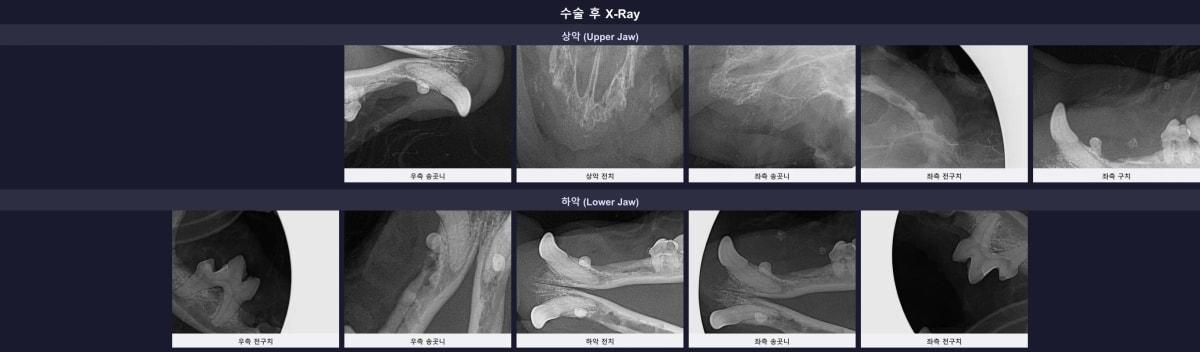

7. 수술 후 엑스레이 검증 및 빠른 회복을 위한 후처치

기나긴 수술이 끝난 후, 발치 부위에 남은 치아 뿌리 조각이나 뼛조각이 없는지 최종 구강 엑스레이를 촬영하여 완벽함을 증명했습니다.

수술 후 잔존 뿌리 없이 깨끗해진 방사선 결과

엑스레이 사진에서 확인할 수 있듯, 잇몸뼈 손상 없이 26개의 치아가 아주 깔끔하게 발치되었습니다. 봉합된 잇몸의 빠른 세포 재생과 통증 완화를 돕기 위해 국소 회복 촉진 레이저 치료를 진행했으며, 남겨진 소중한 치아들에는 불소 도포를 꼼꼼히 마쳐 추가적인 충치나 치석 형성을 억제했습니다.